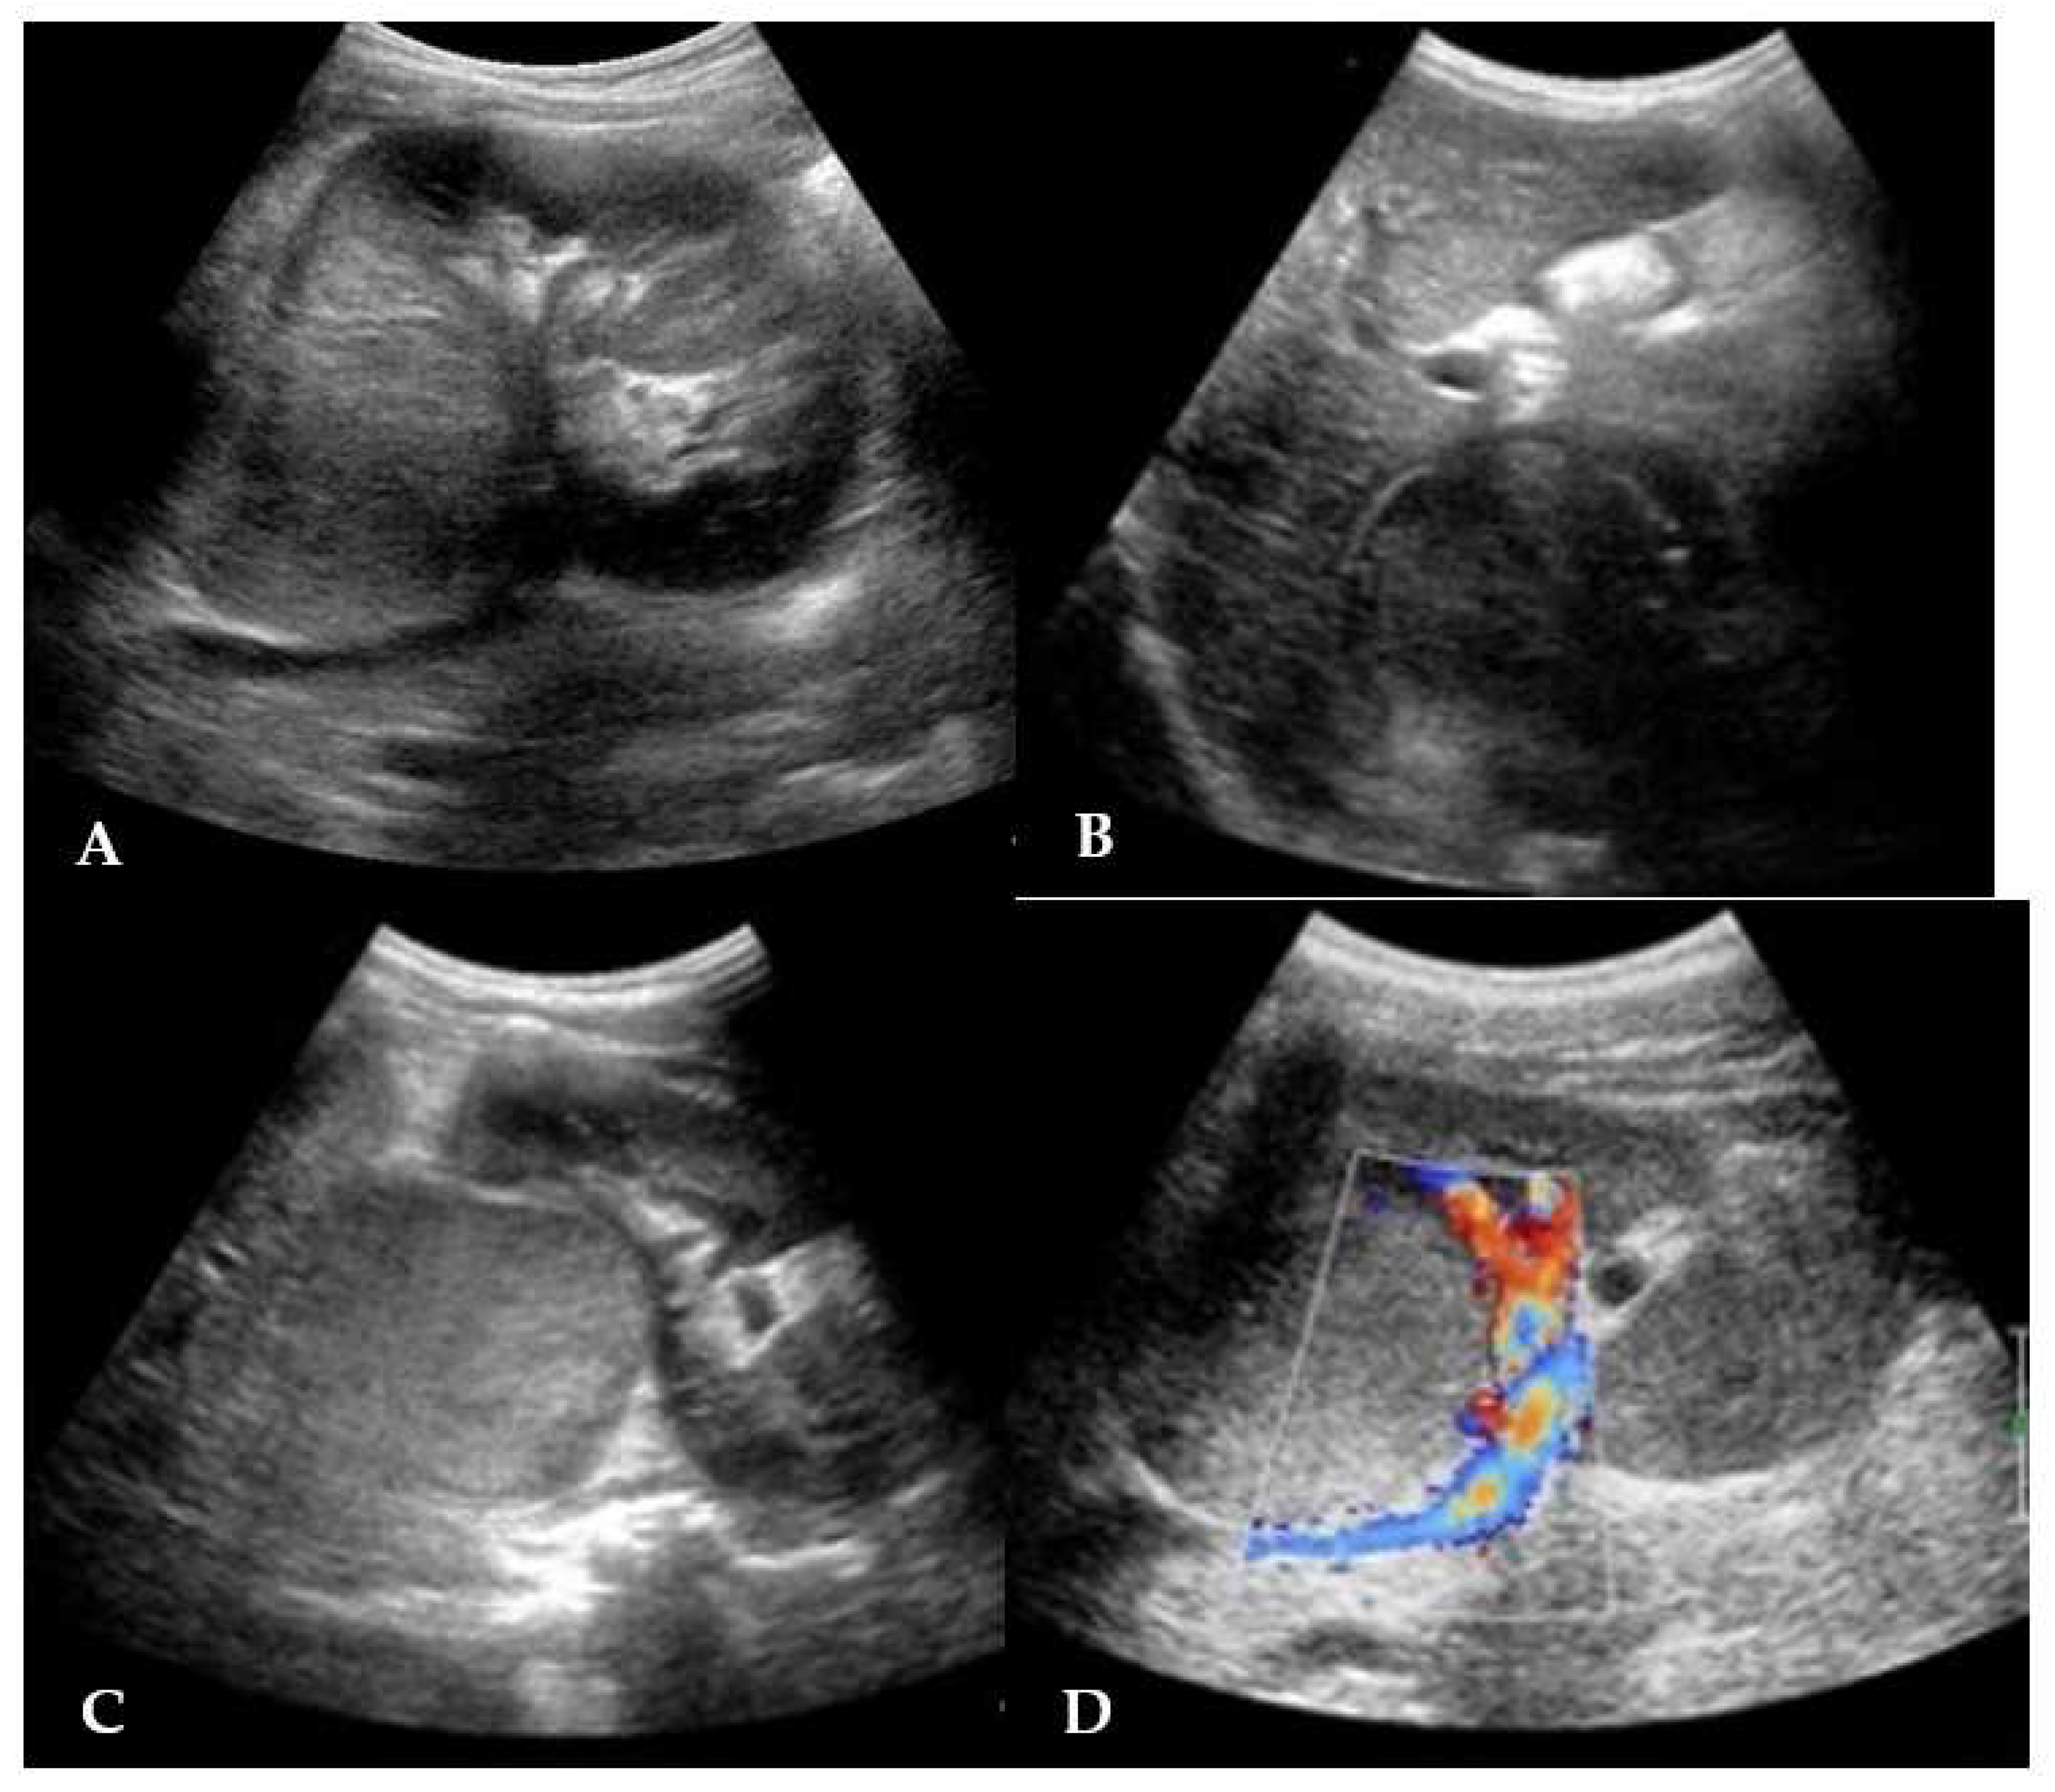

Abdominal US displayed an echogenic solid rounding mass of 3.6 cm diameter in the hepatorenal space. The mass was localized at the upper right renal pole, partially exophytic, with an hypoechoic homogeneous structure and a claw sign; no renal vein involvement was seen and the remaining organs were unharmed (Figure 1).

Figure 1. A-B-C-D. Abdominal US: A- A solid, roundish mass is visible at the upper pole of the right kidney. B- The mass exhibits homogeneous isoechoic content, with a well-distinguishable pseudo-capsule. No signs of involvement with neighboring organs are recognized. C- Transverse scan of the tumor. D-The color-doppler shows no evidence of renal vein thrombosis.